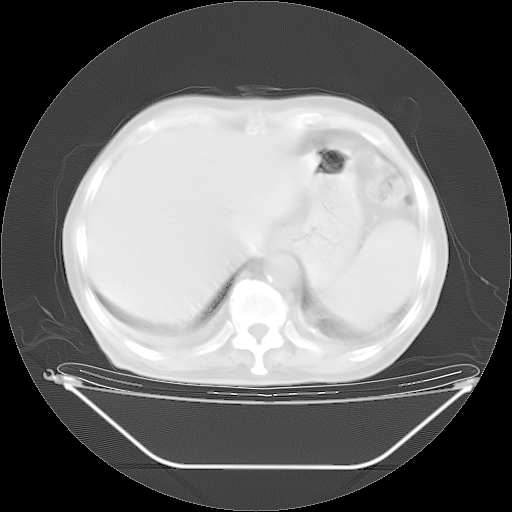

今天复查肺部CT,发现双肺广泛磨玻璃样改变。所以我把3月19日和5月9日相隔50天的肺部CT上传。请大家会诊。

2009年3月19日肺部CT片。

5月9日肺部CT(在4月27日齐鲁医院肺部CT描述部分肺组织磨玻璃样改变,12天后肺组织广泛磨玻璃样改变)